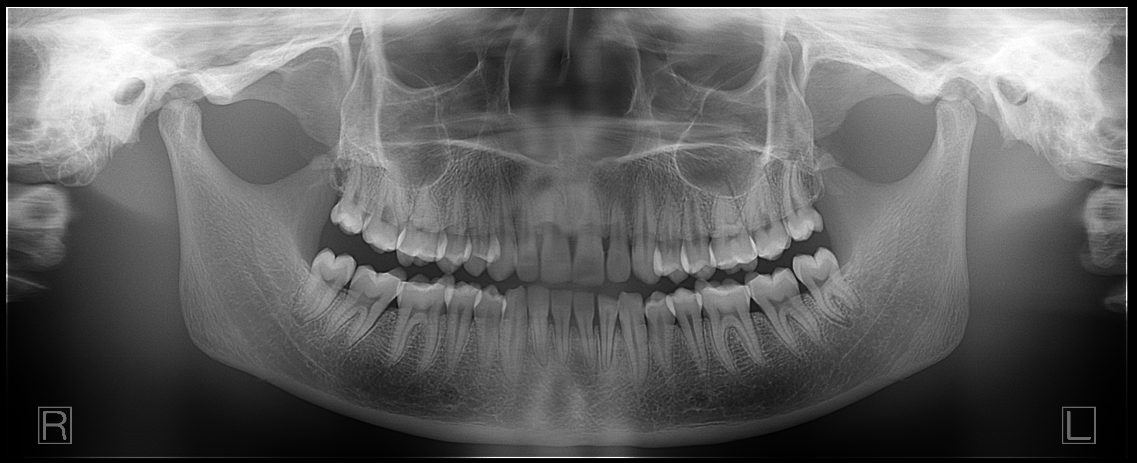

Its direct conversion sensor technology delivers outstanding diagnostic clarity, helping you make confident clinical decisions with less uncertainty.

“These images are awesome”

–Dr. Mark Sheklian, Manasquan, NJ

Every scan captures over 50 different panoramic layers!

With most panoramic x-ray units, the arch of the patient needs to be exactly where the machine wants: along the path where the beam is focused.

- If positioning is not precise, a poor image can result.

- If the patient shifts slightly during the time the operator walks out to initiate the scan, a poor image can result.

- If the patient’s arch doesn’t match the trajectory of the scan, certain anatomy may not be in focus.

- The emergence profile of the anteriors could make it difficult to capture both mandibular and maxillary apices clearly in the panoramic scan.

The Panoura 18S also has Multi-Focal Plane capture capability. This means that every scan captures many layers both forward and backward. This creates a wide “envelope” where much more data is captured around where the patient is positioned.

Great images even if your staff’s technique is less than perfect!